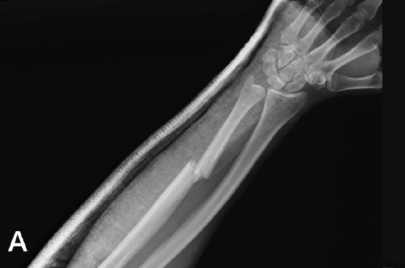

Ballistic Galeazzi Fractures: A Case Series

Timothy Westbrooks , Haley Tornberg , Kevin Heo , Olivia Jagiella-Lodise , Nicole Zelenski

………………………………p.395-400